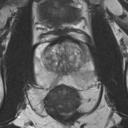

We present a novel technique to discover and exploit weak causal signals directly from images via neural networks for classification purposes. This way, we model how the presence of a feature in one part of the image affects the appearance of another feature in a different part of the image. Our method consists of a convolutional neural network backbone and a causality-factors extractor module, which computes weights to enhance each feature map according to its causal influence in the scene. We developed different architecture variants and empirically evaluated all of our models on two public datasets of prostate MRI images and breast histopathology slides for cancer diagnosis. To confirm our quantitative results, we conduct ablation studies and investigate the explainability of our models via class activation maps. Our findings show that our lightweight block extracts meaningful information and improves the overall classification, together with producing more robust predictions that focus on relevant parts of the image. That is crucial in medical imaging, where accurate and reliable classifications are essential for effective diagnosis and treatment planning.